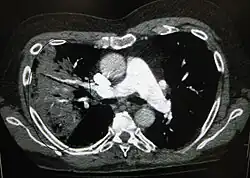

X-ray presentations of pneumonia may be classified as lobar pneumonia, bronchopneumonia, lobular pneumonia, and interstitial pneumonia.[75] Bacterial, community-acquired pneumonia classically show lung consolidation of one lung segmental lobe, which is known as lobar pneumonia.[42] However, findings may vary, and other patterns are common in other types of pneumonia.[42] Aspiration pneumonia may present with bilateral opacities primarily in the bases of the lungs and on the right side.[42] Radiographs of viral pneumonia may appear normal, appear hyper-inflated, have bilateral patchy areas, or present similar to bacterial pneumonia with lobar consolidation.[42] Radiologic findings may not be present in the early stages of the disease, especially in the presence of dehydration, or may be difficult to interpret in the obese or those with a history of lung disease.[24] Complications such as pleural effusion may also be found on chest radiographs. Laterolateral chest radiographs can increase the diagnostic accuracy of lung consolidation and pleural effusion.[41]

A CT scan can give additional information in indeterminate cases[42] and provide more details in those with an unclear chest radiograph (for example occult pneumonia in chronic obstructive pulmonary disease). They can be used to exclude pulmonary embolism and fungal pneumonia, and detect lung abscesses in those who are not responding to treatments.[41] However, CT scans are more expensive, have a higher dose of radiation, and cannot be done at bedside.[41]